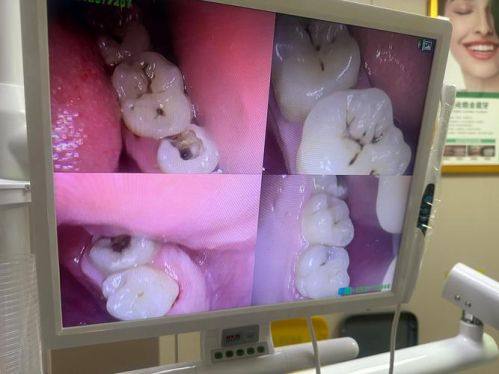

口腔内科:可开展补牙、牙髓治疗、根管治疗等项目,配备牙髓测量仪、热牙胶充填设备等专精设备,能精细处理龋齿、牙髓炎等各类口内问题。